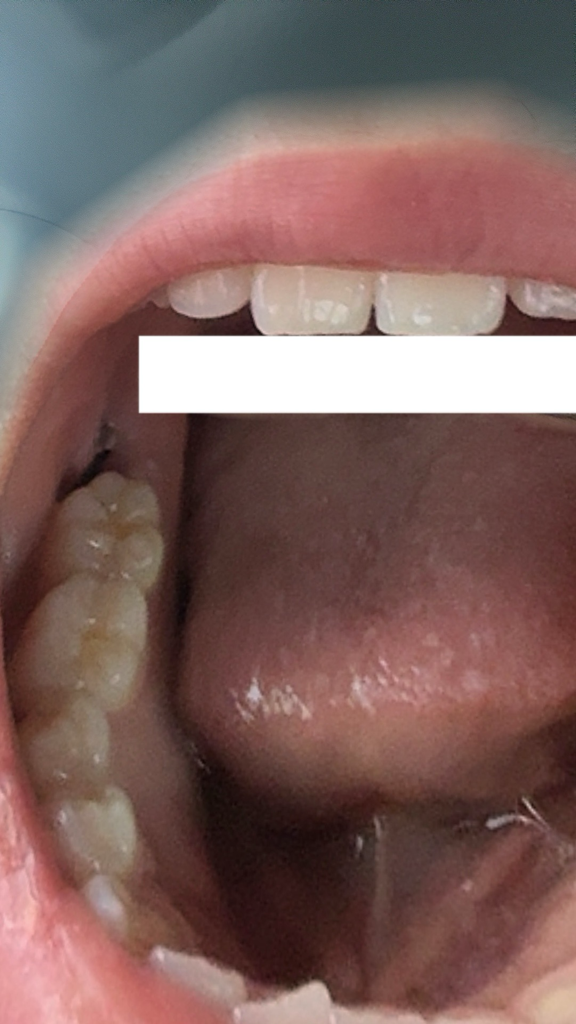

매복 사랑니 발치 후 이건 뭔가요?

저기 사랑니 쪽에 갑자기 흰 색으로 달랑 달랑 거리는게 생겼는데 뭔가교? 살점인가요 아님 실밥에 이물질 낀 건가요

저게 생기고 이 사진으로 가르킨 부위가 너무너무 아파서 진통제도 안 통하는데 혹시 저 흰색 튀어나온 걸 그냥 떼도 되나요? 참고로 이물질은 식 후 20분 이내에 빼고 이 쪽 이빨론 음식도 안 씹어요 ㅠㅠ

사랑니 빼고나서 잇몸이 치유되는과정중에 생기는 자연스러운 현상이니 건들지 않으시는게 좋습니다. 아직 붓기가 빠지지 않으셔서 그런거 같습니다.

현재 실밥이 나온 것으로 보이며, 해당부위에 이물질이 낀 겨우 통증이 유바될가능성이 있습니다. 임의로제거는 하지 마고, 치과에 방문하여 상태 확인후 조치를 받길 권합니다.

사랑니를 발치하고 나면 사랑니를 발치한 부위에 잇몸이 차오르면서 부어오르거나 잇몸 조직이 너덜거릴 수 있습니다. 대부분 시간이 지나면서 괜찮아지며 해당 부위를 자극하지 않는 것이 좋습니다.